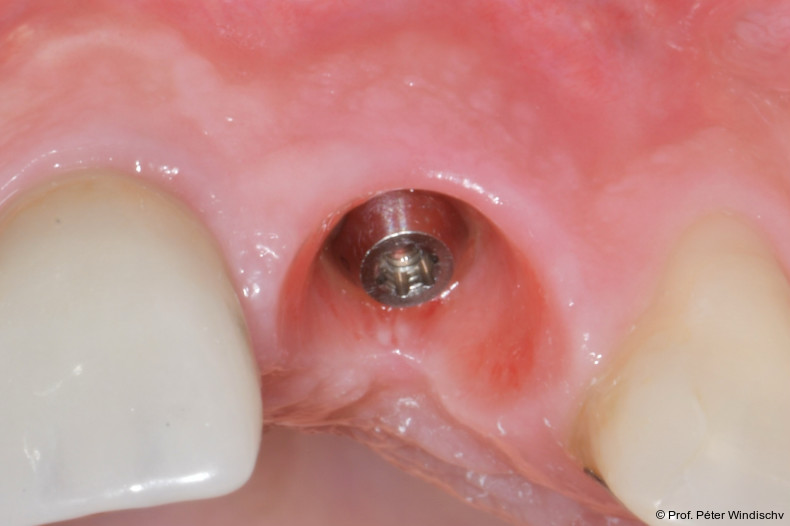

Nach einer Einwirkzeit von mindestens 60 Sekunden (Abb. 6) wurde die Tasche und die Implantatoberfläche gründlich mit Titanküretten instrumentiert. Während der Instrumentierung wurde das Reinigungsgel mehrmals in die Tasche appliziert und 60 Sekunden einwirken gelassen (ca. fünf bis sechs Mal), jeweils gefolgt von weiteren Instrumentierungszyklen. Dies wurde so oft wiederholt, bis keine sichtbaren Konkremente mehr aus der Tasche kamen (Abb. 7).

Nach Abschluss der submarginalen Instrumentierung wurde die Tasche mit Kochsalzlösung gespült und eine hochkonzentrierte, vernetzte Hyaluronsäure (xHyA, hyaDENT BG) in den Defekt appliziert (Abb. 8).